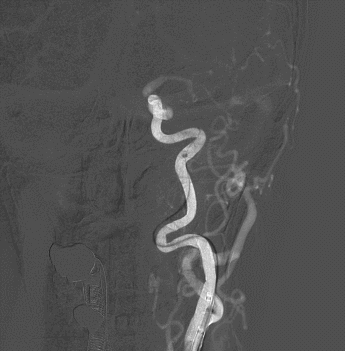

撤出球囊导管,交换送入XT-27支架微导管至左侧大脑中动脉M1段,顺支架微导管送入Neuroform EZ 4.0-20mm支架,准确对位并释放支架。

将6F 115cm SKATHI远端通路导管撤至左侧颈内动脉C1起始,多角度造影显示左侧颈内动脉眼动脉段狭窄明显改善,颈内动脉通畅,颅内血流改善。